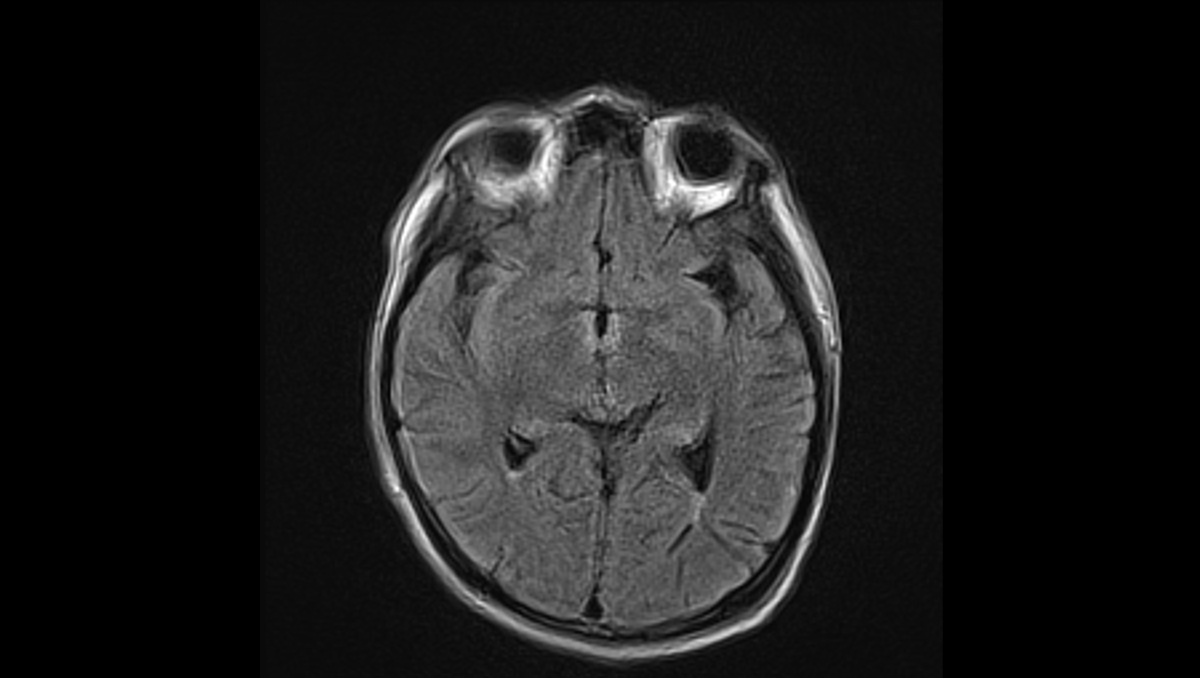

症例1:28歳男性

- 【主訴】

- 体動困難、呂律不良

- 【現病歴】

-

- 4か月ほど前から歩行時の息切れあり、1か月前から下肢の疼痛が出現、1週間前からはベッド上で生活していた。

- 3日前から呂律が緩慢となり、増悪したため、父親が救急要請。

- 医療機関の受診歴なし

- 高校卒業後は就職せず、自宅でゲームをする時間が長かった。

- 救急隊より、自宅はゴミ屋敷の状態であった、と。

- 【既往歴】

- JCS I-3

BT 37.6℃, BP 147/58mmHg, HR 120/min, SpO2 99% - 【血液検査】

- WBC 11000/µL, Hb 9.7g/dL, CRP 4.94mg/dL

低血糖なし、電解質異常なし、甲状腺機能異常なし

COVID-19とインフルエンザは陰性